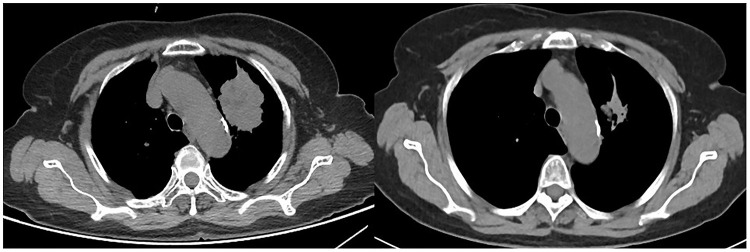

Methods: A total of 107 patients with previously ICIs-treated advanced NSCLC who received anlotinib-related regimens or single-agent chemotherapy in clinical practice were included in this study retrospectively. The anlotinib group (AG) included 54 patients who received anlotinib-related regimens, and the chemotherapy group (CG) consisted of 53 patients who received single-agent chemotherapy. This study retrospectively collected the efficacy and safety data during the patients' therapeutic process and performed regular follow-up to obtain long-term survival data. Clinical outcomes and safety profiles between AG and CG were analyzed and compared.

Results: Best overall response of the 107 patients with previously ICIs-treated advanced NSCLC suggested that objective response rates of AG and CG were 24.1% and 11.3%, respectively; no statistically significant difference was observed (P = 0.084). Disease control rates were 79.6% and 54.7%, respectively (P = 0.006). Furthermore, the median PFS of AG and CG were 6.3 months (95% CI = 0.91-11.69) and 2.8 months (95% CI = 2.32-3.28), respectively, which showed a statistically significant difference (P = 0.002). The median OS in AG and CG were 16.1 months (95% CI = 12.28-19.92) and 10.1 months (95% CI = 3.99-16.21), respectively, which also exhibited a statistically significant difference (P = 0.015). Incidence of adverse reactions with all grades in AG and CG were 85.2% and 83.0%, respectively, grade ≥3 adverse reactions occurred in 40.7% and 45.3%, respectively. Common adverse reactions of patients in AG included fatigue, hypertension, nausea and vomiting, and hematologic toxicity, while patients in CG commonly experienced fatigue, hematologic toxicity, nausea and vomiting, and liver toxicity.

Conclusion: Among patients with previously ICIs-treated advanced NSCLC, anlotinib-related therapeutic regimens demonstrated encouraging efficacy and a tolerable safety profile compared with the single-agent chemotherapy regimen. This conclusion still needs further validation in prospective clinical trials.